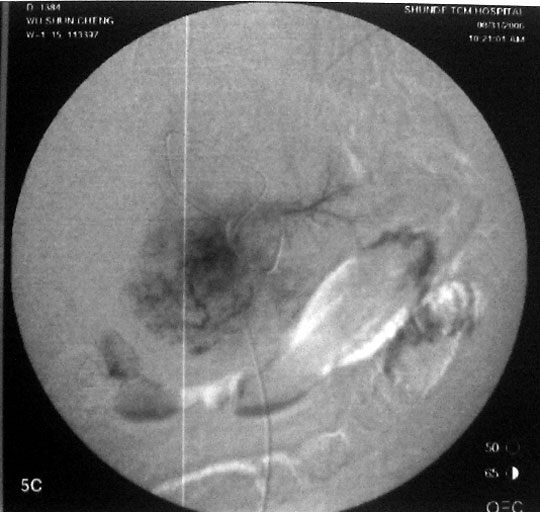

介入治疗过程:右股动脉穿刺,引入导丝导管,超选入肝固有动脉,造影显示肝右动脉肿瘤供血,圆球样肿瘤边界清楚。采用同轴导管进一步超选入右肝动脉、肿瘤血管边缘,注入化疗药+碘油混合剂7ml。

图1-3:导管进入肿瘤血管后造影,分别显示造影早期、中期、末期肿瘤情况。

图4:栓塞治疗后,肿瘤已为化疗药+碘油混合剂充填。